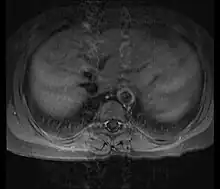

![]() | |

| Left anterior oblique angiographic image of Takayasu's arteritis showing areas of stenosis in multiple great vessels | |